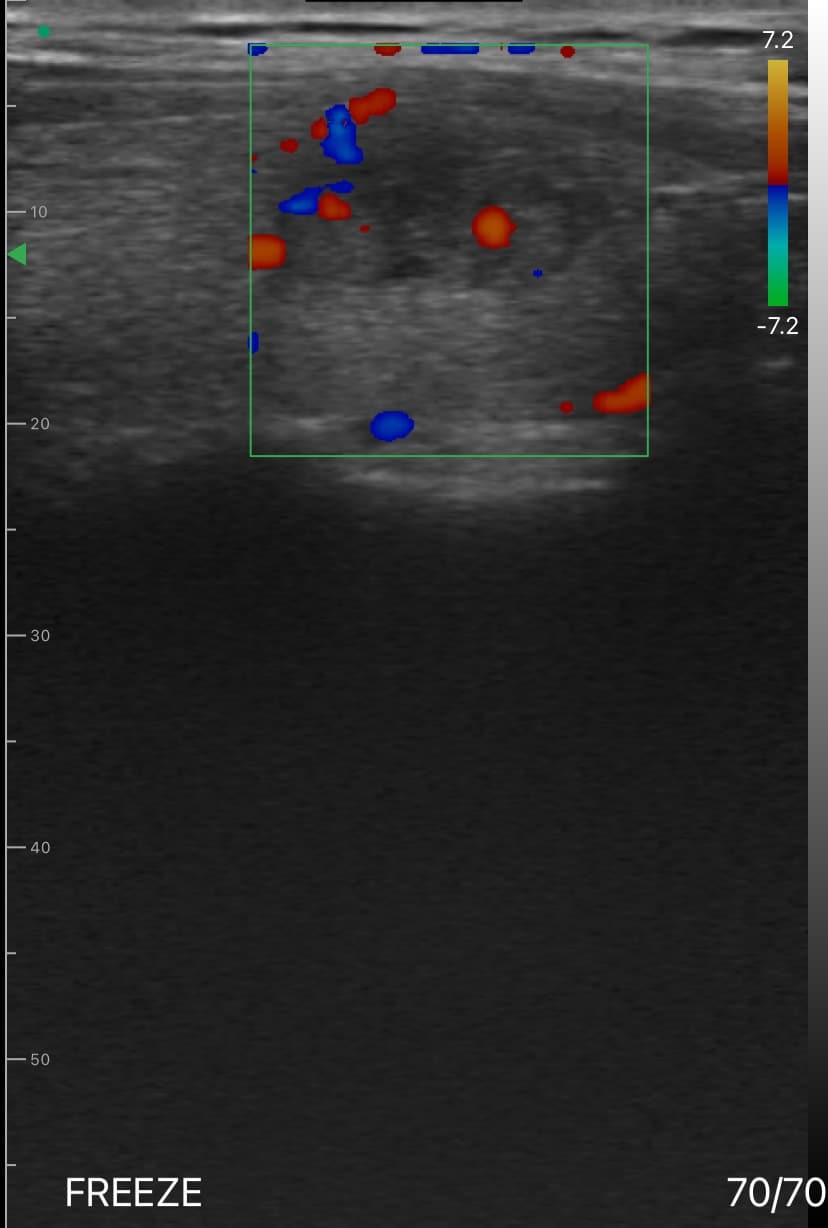

Dr. Sophia Kim used the DrSono Tri-scan Max to monitor the growth of a fetus at 28 weeks of gestation in a patient with a history of intrauterine growth restriction (IUGR). By measuring the fetal biparietal diameter (BPD), head circumference (HC), abdominal circumference (AC), and femur length (FL), she confirmed that the fetus was growing appropriately, alleviating the patient's concerns.

In addition to performing detailed biometric measurements to estimate fetal weight, Dr. Kim utilized the color Doppler mode to assess the umbilical cord blood flow, ensuring proper fetal circulation. She also conducted a thorough evaluation of the fetal spine and lateral ventricles, confirming normal development. Amniotic fluid levels and fetal movement were also checked, providing a comprehensive overview of the fetus's well-being.

Performed detailed biometric measurements to estimate fetal weight.

Checked for abnormalities in amniotic fluid levels and fetal movement.